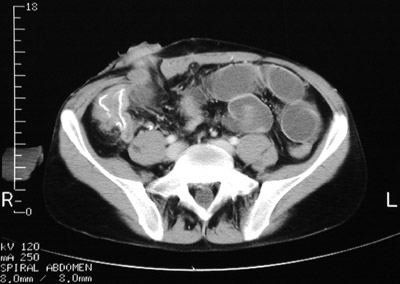

Postoperatively, there are dilated loops of small bowel in this abdominal CT scan. Contrast was administered, but it has not made its way to the small intestine. An ileostomy stoma is present as well.